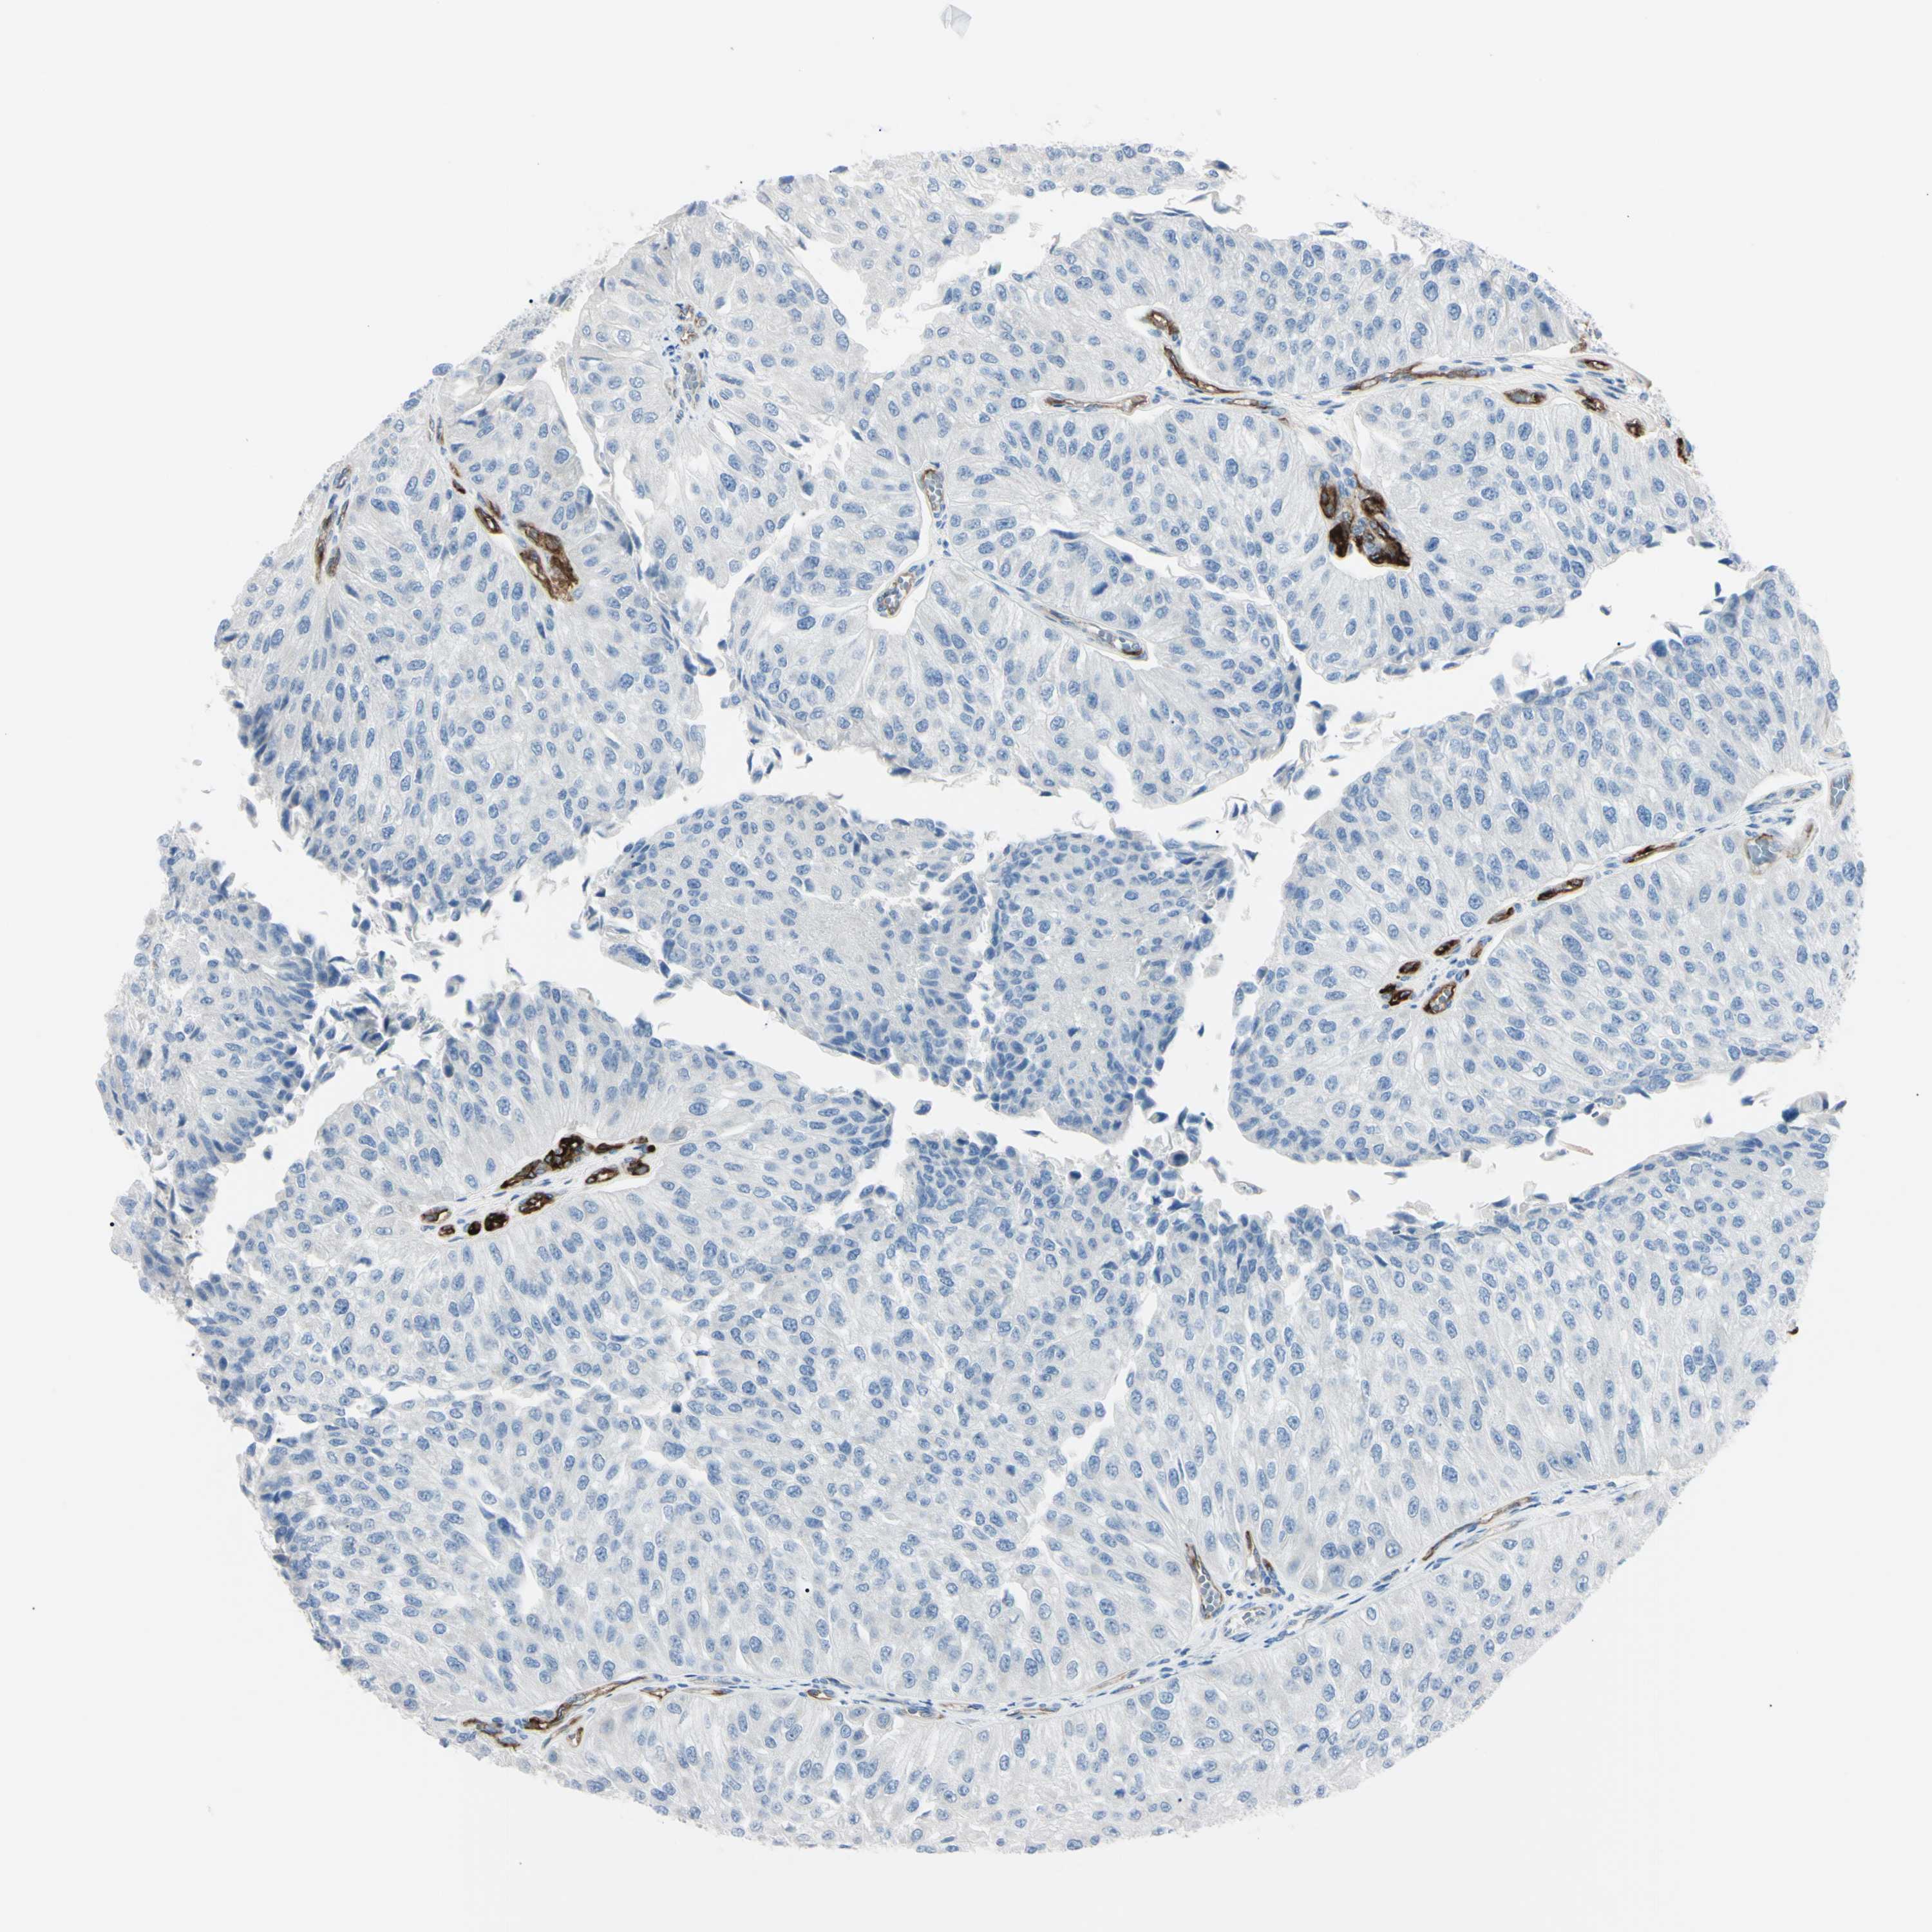

UROTHELIAL CANCER - Protein expressioni

A mouse-over function shows sample information and annotation data. Click on an image to view it in a full screen mode. Samples can be filtered based on level of antibody staining by selecting one or several of the following categories: high, medium, low and not detected. The assay and annotation is described here.

Note that samples used for immunohistochemistry by the Human Protein Atlas do not correspond to samples in the TCGA dataset.

Antibody stainingi

Antibody staining in the annotated cell types in the current human tissue is reported as not detected, low, medium, or high, based on conventional immunohistochemistry profiling in selected tissues. This score is based on the combination of the staining intensity and fraction of stained cells.

Each image is clickable and will lead to virtual microscopy that enables deeper exploration of all samples and also displays staining intensity scores, fraction scores and subcellular localization as well as patient and tissue information for each sample.

Antibody HPA010593

Antibody CAB001451

Staining

High

Medium

Low

Not detected

Intensity

Strong

Moderate

Weak

Negative

Quantity

>75%

75%-25%

<25%

None

Location

Nuclear

Cytoplasmic/membranous

Cytoplasmic/membranous,nuclear

Urothelial carcinoma, Low grade

Urothelial carcinoma, High grade

Adenocarcinoma, NOS